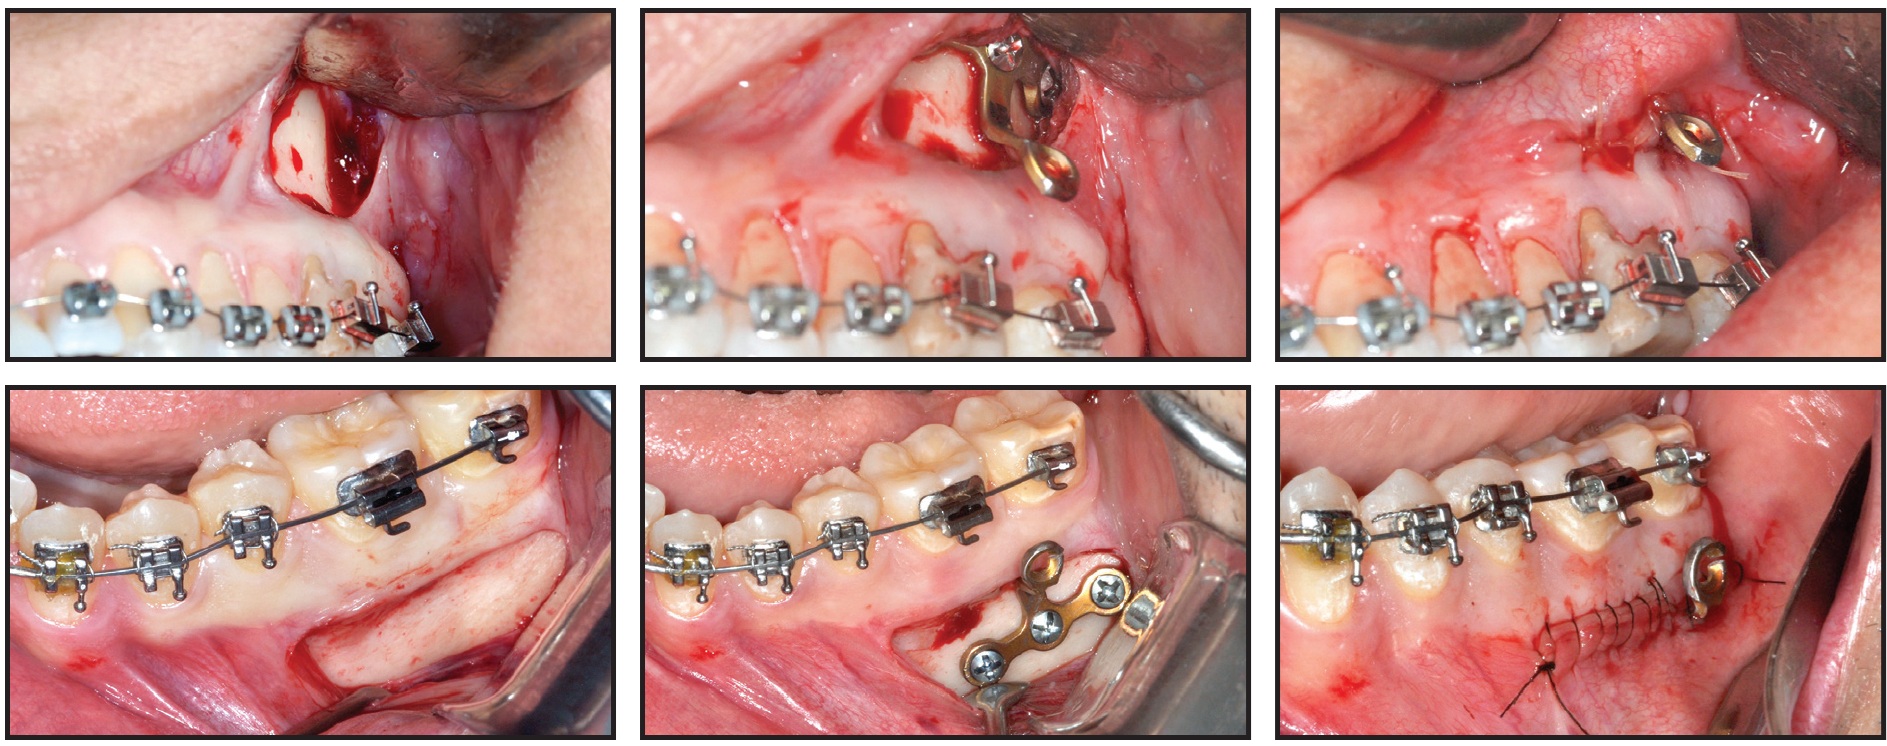

The miniplates were inserted under local anesthesia. Surgery was performed through a linear incision followed by mucoperiosteal detachment and exposure of the target area (Fig. 4).

Fig. 4 Surgical procedure for installing T-shaped miniplates, which are bent to conform to patient anatomy and align with incision, keeping miniplates away from gingival margins and thus allowing proper hygiene.

Models made by rapid prototyping were used to facilitate adjustment of the miniplates, reducing the time required for surgery and thus minimizing postoperative edema. Each miniplate was bent to adapt to the patient’s anatomy and affixed using screws 2mm in diameter and 5mm in length. The region was then sutured, with one link of the miniplate left exposed for force attachment.